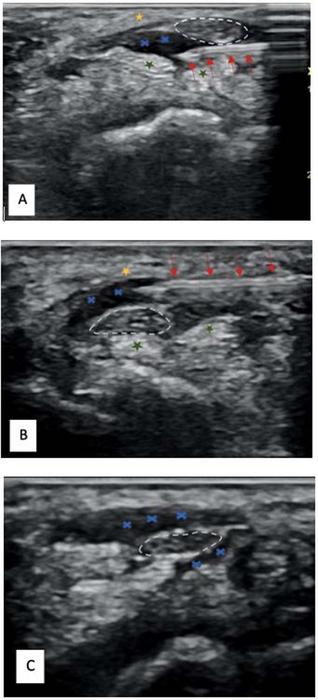

But this new study shows that a technique called hydrodissection effectively treats nerve entrapments without the need for surgery or corticosteroids. It involves the injection of a liquid, usually saline, into a nerve to separate it from the surrounding tissue. Ultrasound guidance is used to accurately identify nerves.

For this randomized control trial, Dr. Bose and colleagues enrolled a total of 63 patients suffering from carpal tunnel syndrome. Researchers used the Boston Carpal Tunnel Questionnaire (BCTQ), the Visual Analog of Pain (VAS), and cross-sectional area ultrasounds of the median nerve to assess patient pain and symptoms before and after the procedure. The 63 patients were divided into three groups. Group one received ultrasound-guided hydrodissection with just a saline injection. Group two received ultrasound-guided hydrodissection with an injection mixture of saline and corticosteroid. Group three received just an ultrasound-guided corticosteroid injection with no hydrodissection.

Follow-up was done at four weeks, 12 weeks and six months. At the four-week mark, all three groups of patients showed a reduction in pain. By the 12-week and six-month mark, both groups that received ultrasound-guided hydrodissection showed further improvement while the group that received just a corticosteroid injection reported a recurrence of symptoms and an increase in BCTQ and VAS scores.

Additionally, ultrasounds showed a significant reduction of median nerve cross-sectional area in both hydrodissection groups. Group one showed a reduction of 43%, and group two showed 46%. Group three showed only an 11% reduction.